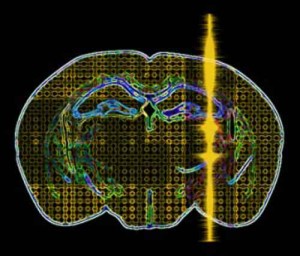

Gli ultrasuoni, indirizzati verso una specifica regione del cervello, possono modulare l'attivita' di questo organo potenziando la percezione e la...